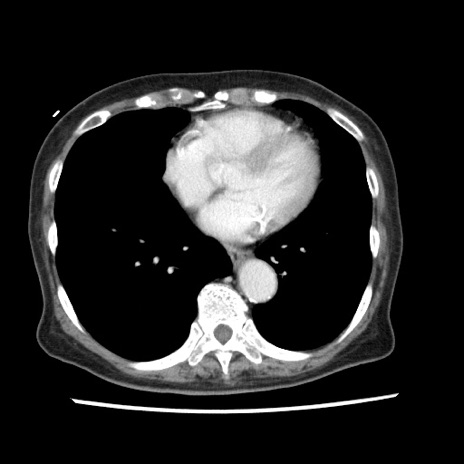

冠状断像

【症例】80歳代女性

【主訴】腹痛

【現病歴】8時間前から腹痛あり来院。

【既往歴】糖尿病、脂質異常症、子宮体癌にて子宮全摘術

【身体所見】意識清明・会話良好だが腹痛で苦悶様、全腹部にわたって反跳痛と圧痛あり

【データ】WBC 13600、CRP 0.14、LDH 224、CK 90